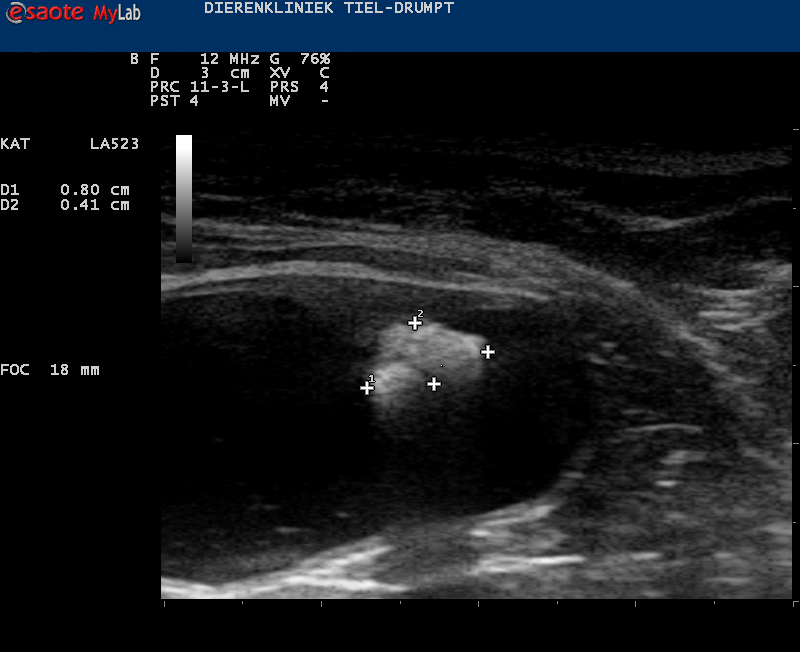

Zo kan er sprake zijn van zwelling of een gezwel bij de penis of een verstopping in de plasbuis door bijvoorbeeld samengeklonterd gruis, een blaassteentje of een plug (dit wordt gevormd door eiwitten, cellen, etc) die een verstopping kunnen geven.Ook structuren in de blaas kunnen de uitmonding verstoppen, zoals steentjes, poliepen, gezwellen, etc.

De prognose van de behandeling bij een verstopping van de penis, zoals bij de plaskater, hangt sterk af van hoe snel er ingegrepen kan worden, de oorzaak van de verstopping en de wijze van behandelen.Er kan bijvoorbeeld gruis aanwezig zijn wat zeer goed te bestrijden is met een medisch dieet. Er bestaat echter ook blaasgruis dat niet goed met een dieet te behandelen is. Als blaasgruis langer onbehandeld aanwezig is, dan kan dit samenklonteren tot stenen.

Deze zullen operatief verwijderd moeten worden want anders blijft er aanleiding tot ontstekingen van de blaas en mogelijk nieuwe verstoppingen. Ook de mate van zwelling in de plasbuis kan zorgen voor risico’s van recidief. Indien de oorzaak een tumor is dan wordt de prognose vaak slechter. Dit hangt echter ook af van de locatie van de tumor.